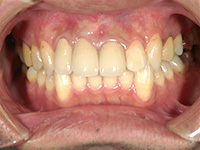

結合組織移植術

右上3番、4番の歯の根が露出していたため、上顎の裏側から結合組織を移植しました。

他の箇所とかわりなく、きれいな歯ぐきになりました。

上顎裏側の結合組織を摘出しています。術後の傷も、きれいに治りました。